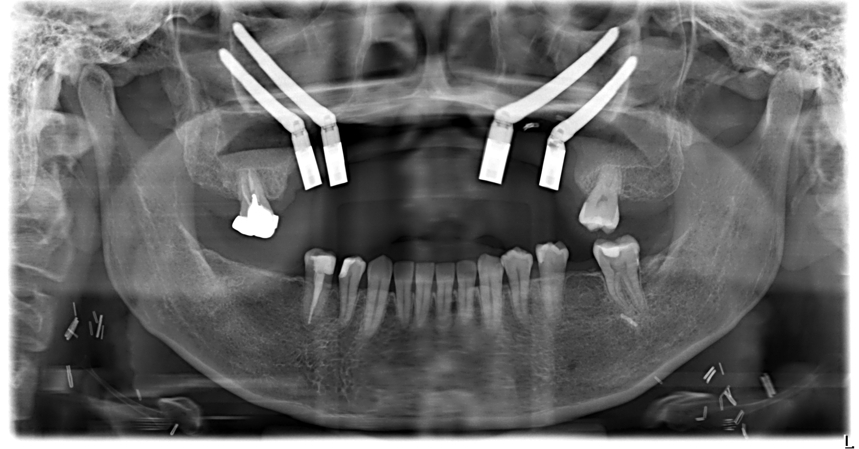

40歲的許小姐於2024年前往中山醫學大學附設醫院(以下簡稱中山附醫)口腔顎面外科就醫,確診為上顎牙齦癌,須切除大範圍上顎骨,不僅影響外觀,口內鄰近腫瘤的10顆牙齒亦需一併拔除。醫療團隊於術前運用電腦數位模擬技術,精準規劃腫瘤切除範圍、術後牙齒重建位置,並模擬將植體植入顴骨,以彌補上顎骨缺損。

手術當日,由中山附醫口腔顎面外科邱昱瑋、陳怡孜及陳珮吟三位主治醫師組成的醫療團隊主導,結合電腦數位模擬、切割導版與電腦導航系統輔助,依序完成腫瘤切除範圍確認、術後牙齒排列模擬,以及顴骨植體植入定位。最終於同一日內一次完成上顎口腔癌腫瘤切除、頸部淋巴清除、顴骨植牙及游離皮瓣重建等複雜手術,大幅縮短整體治療時程,降低患者身體負擔。術後,許小姐已成功恢復正常咀嚼功能,生活品質明顯提升。

中山附醫口腔顎面外科自2018年起全面導入電腦數位模擬手術與精密導航技術,廣泛應用於顏面骨折外傷、正顎手術、腫瘤切除及重建等領域。透過術前精準規劃,不僅可減少手術傷口與誤差,也能提升手術安全性與準確度,協助患者同時重建外觀與功能,順利回歸正常生活。